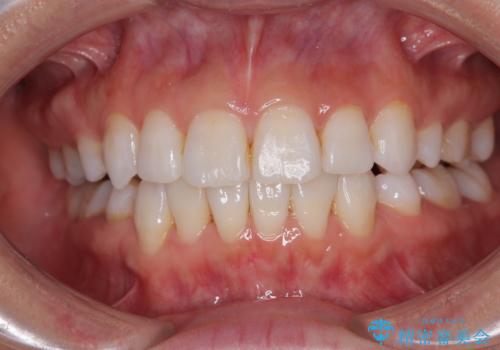

- 上下前歯の後戻りを気にして来院された患者様です。

インビザラインでの治療を希望されていて、デコボコの程度が中等度であり、安価なパッケージにて対応可能と判断されたため、インビザライン・モデレートを用いて矯正治療を行うこととしました。

インビザライン・モデレートは、製作できるアライナーの枚数に制限があるため、移動可能な量に限りがあるものの、インビザライン・ライトよりも枚数が多いため、幅広い症例に対応可能です。